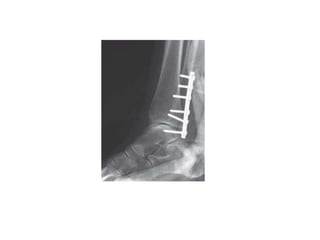

Fixation techniques:

Ankle fracture

Fixation of lateral

malleolus

Simple oblique

fracture

(SER 3,4)

Inter frag screw

+/- neutralization plate

Or

Malleolar screw

Simple transverse

(PER 3,4)

Compression plate

Comminuted fracture

(PAB 3)

Bridge platting

IM nailing